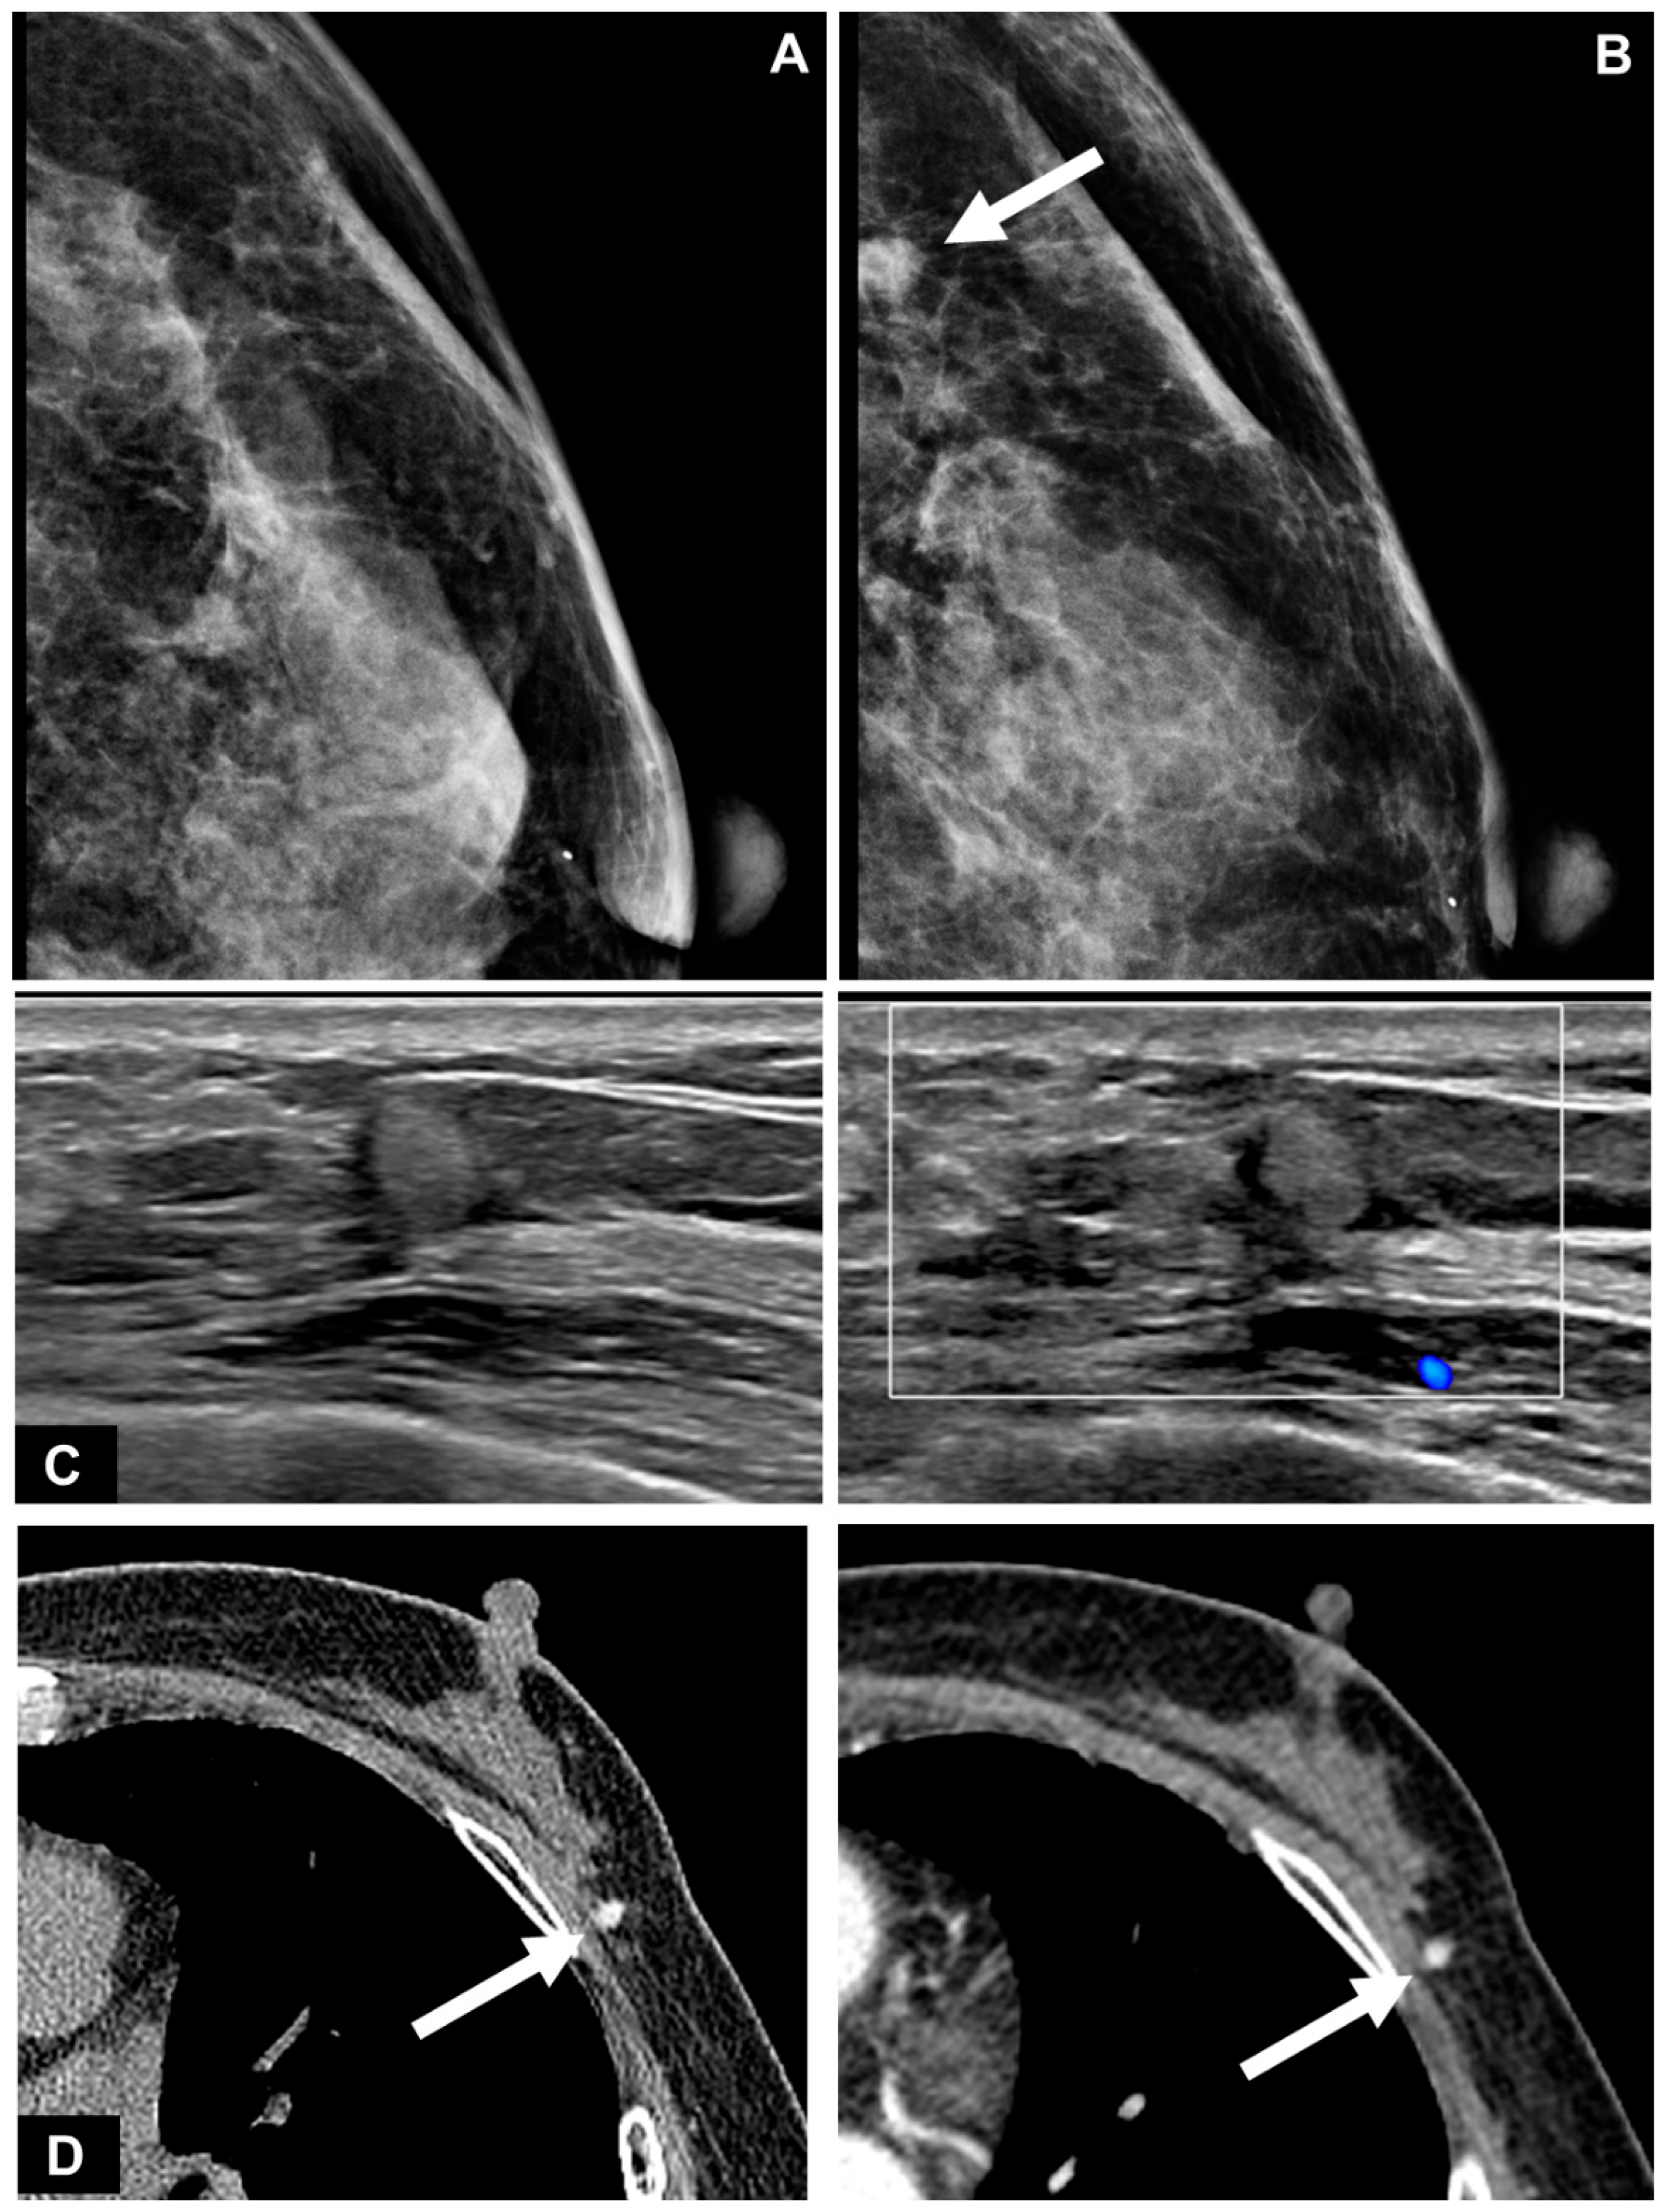

| Mass | 18/18 (100.0%) |

| Non-mass lesion | 0/18 (0.0%) |

| Size (cm, median) | 0.8 (0.6, 1.1) |

| Shape | |

| Round or oval | 9/18 (50.0%) |

| Tubular | 1/18 (5.6%) |

| Irregular | 8/18 (44.4%) |

| Margin | |

| Circumscribed | 8/18 (44.4%) |

| Not circumscribed | 10/18 (55.6%) |

| Echogenicity | |

| Hypoechoic | 3/18 (16.7%) |

| Isoechoic | 8/18 (44.4%) |

| Hyperechoic | 7/18 (38.9%) |

| Echogenic halo | 5/18 (27.8%) |

| Taller-than-wide | 11/18 (61.1%) |

| Posterior acoustic shadowing | 3/18 (16.7%) |

| Hypervascularity | 4/18 (22.2%) |

| Location | |

| Skin~subcutaneous layer | 3/17 (17.6%) |

| Subcutaneous layer | 2/17 (11.8%) |

| Subcutaneous layer~breast parenchyma | 9/17 (52.9%) |

| Breast parenchyma | 3/17 (17.6%) |

| BI-RADS category | |

| 3 | 7/18 (38.9%) |

| 4A | 9/18 (50.0%) |

| 4B | 1/18 (5.6%) |

| 4C | 1/18 (5.6%) |